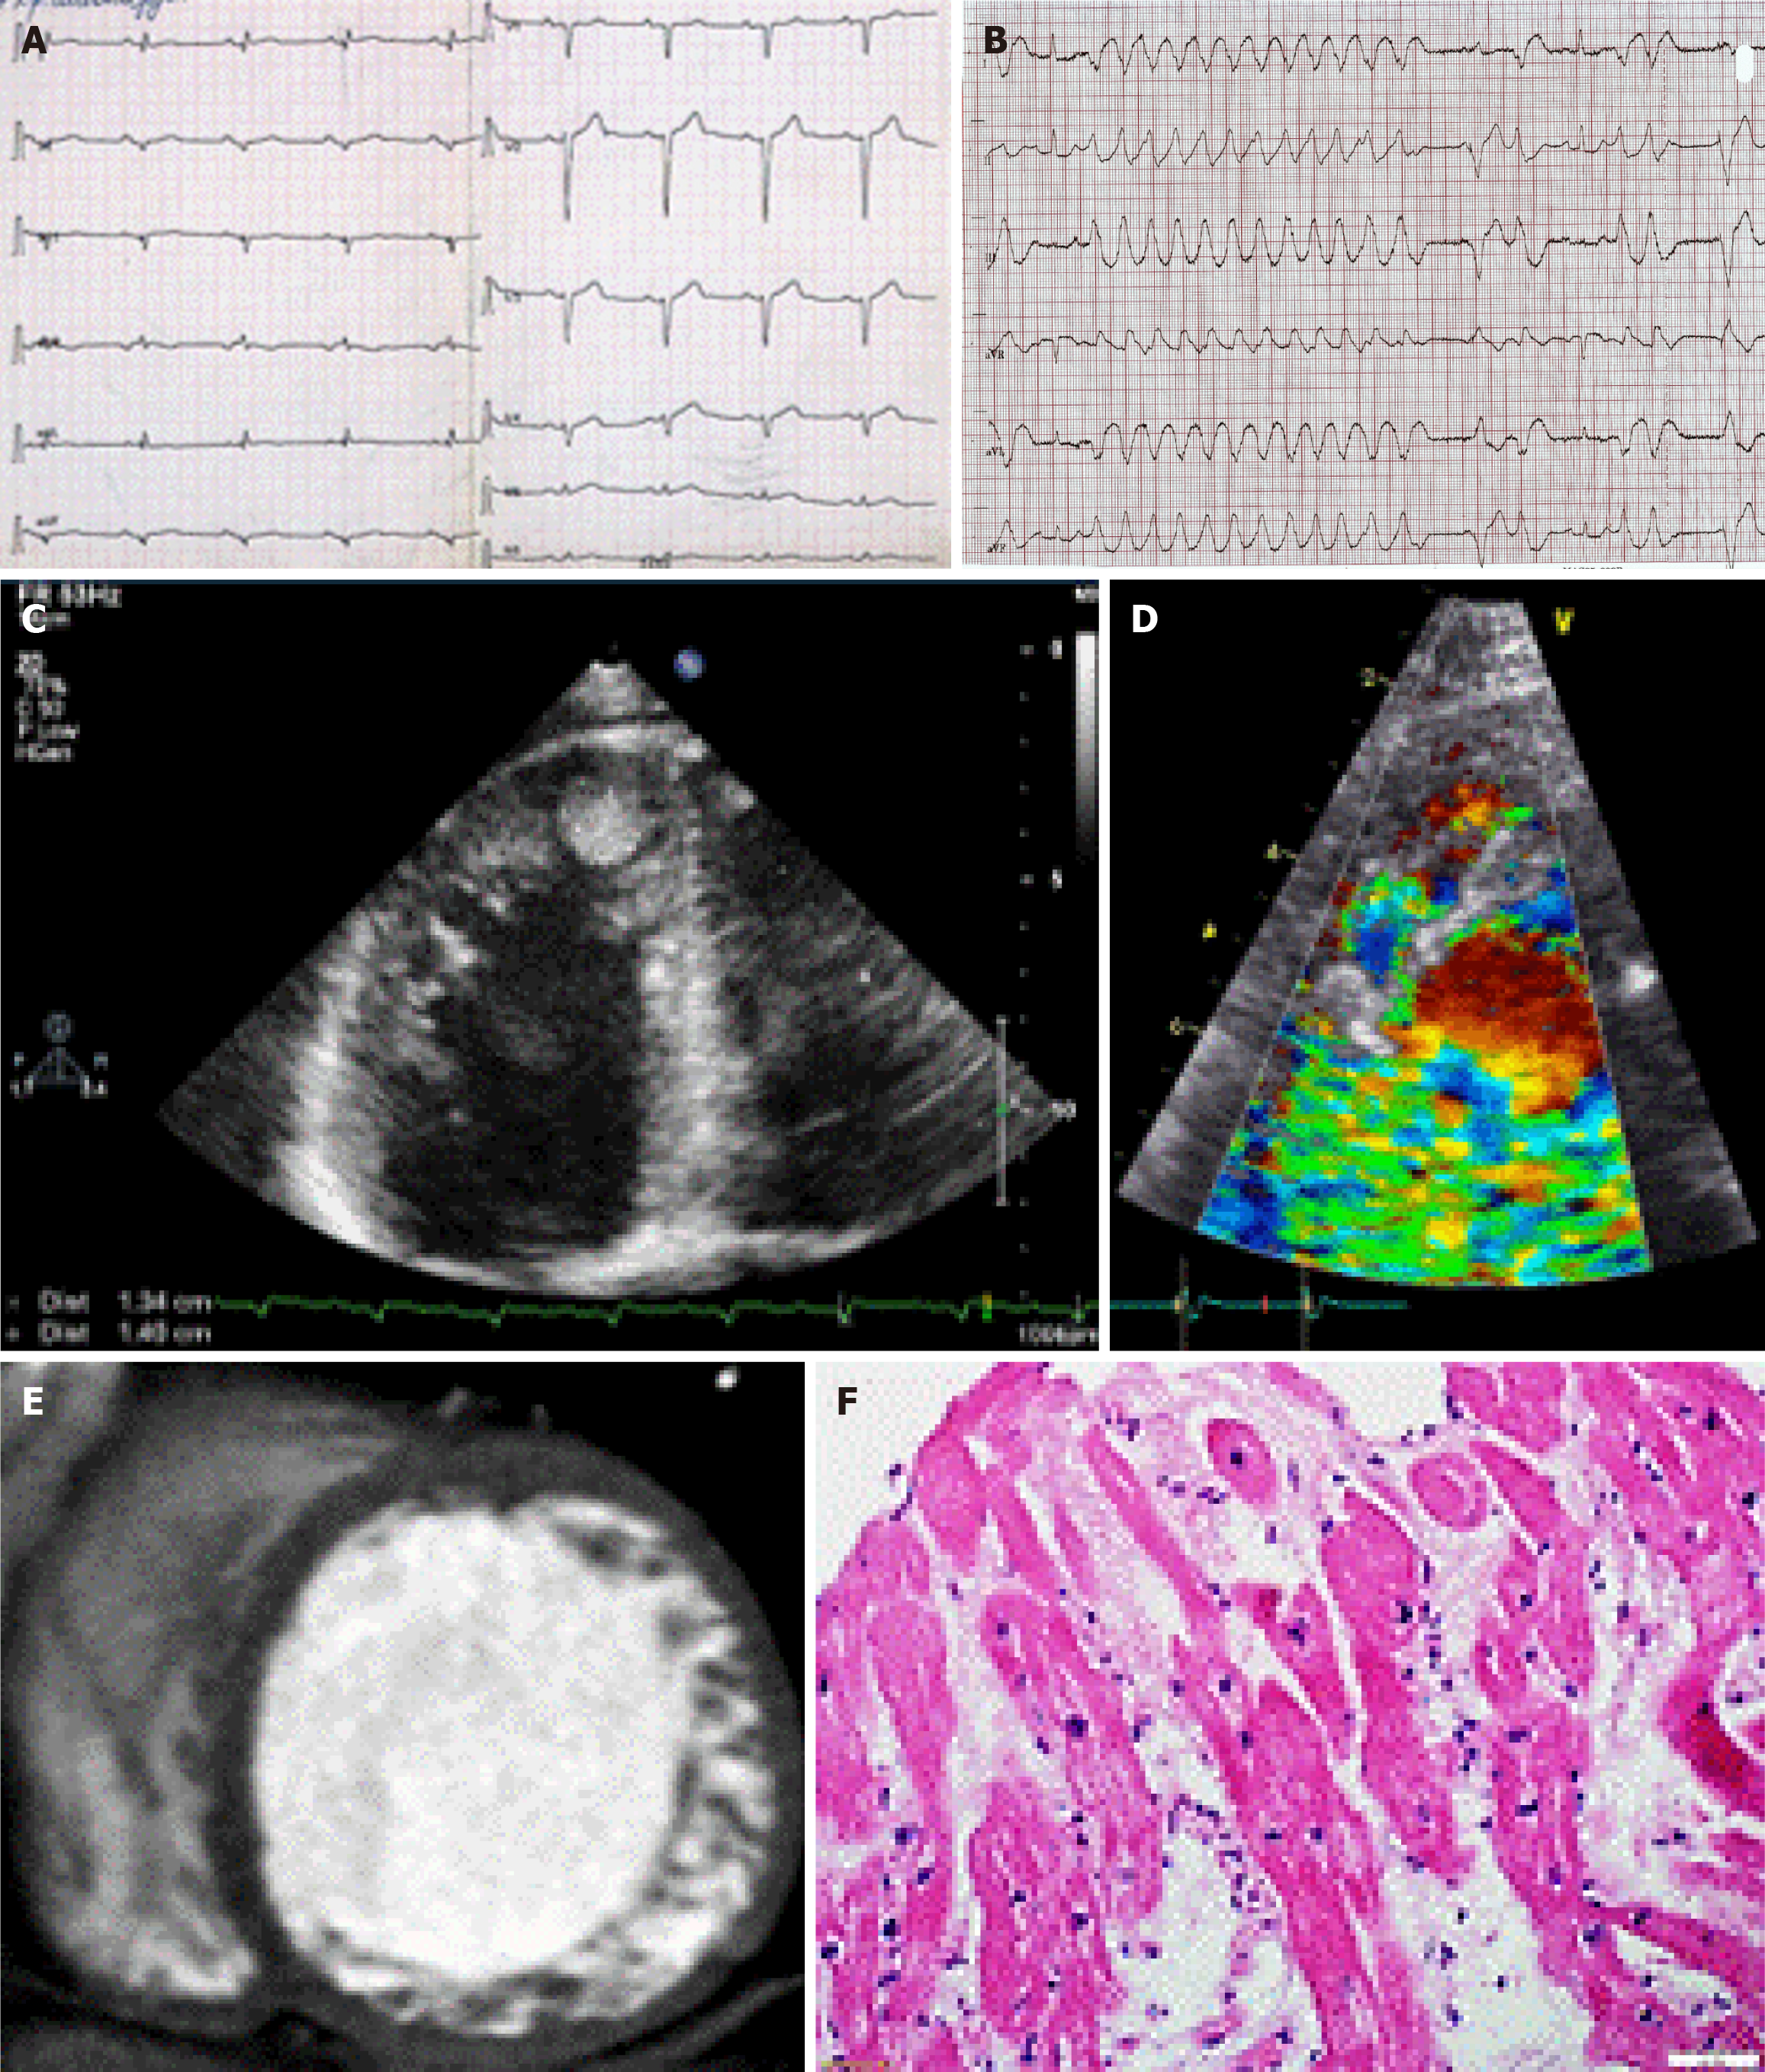

Electrocardiography (ECG, n = 125), echocardiography (n = 125), 24-hour ECG monitoring (n = 125), coronary angiography (n = 33), cardiac MRI (n = 60), cardiac computed tomography (n = 90), and laboratory tests were conducted. The diagnosis of LVNC was confirmed by two imaging modalities in 74 cases and by three imaging modalities in 21 cases (Figure 1). To diagnose superimposed myocarditis we assessed the level of anti-heart antibodies by indirect immunofluorescence (n = 102) and/or performed pathological examination of the myocardium (n = 26), including endomyo

The study included 125 adult patients with LVNC, including 74 males (59.2%) and 51 females (40.8%) with a mean age of 46.4 ± 15.1 years. The median follow-up was 14 months (range: 4.0-41.0). The principal manifestations of LVNC were heart failure [n = 46, 37.0%, New York Heart Association (NYHA) class III-IV], rhythm abnormalities (n = 92, 73.6%), conduction abnormalities (n = 66, 52.8%; Figure 1), thromboembolic events (n = 29, 23.2%; Figure 1), and SCD (n = 11, 8.9%). Echocardiography showed a decrease in myocardial contractility and dilatation of the left heart chambers. The mean left ventricular ejection fraction (LVEF) was 38.6% ± 14.0% (Table 1).

The diagnosis of superimposed myocarditis was based on the results of the myocardial morphological study (Figure 1) or complex noninvasive clinical, laboratory, and instrumental examination based on a previously developed algorithm[20]. The frequency of combined LVNC and myocarditis was 54.0% (n = 67). Pathogenic mutations were detected in 13 patients (10.4%) in the MYBPC3, MYH7, titin, desmoplakin, desmin, and lysosomal associated membrane protein 2 genes. Variants with unknown clinical significance in the MYH7, MYBPC3, actin, alpha, cardiac muscle 1, and transmembrane protein 43 genes were detected in 7 patients.